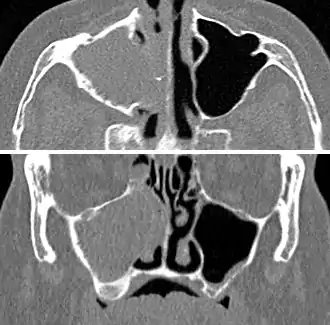

For cases of maxillary sinusitis, limited field CBCT imaging, as compared to periapical radiographs, improves the ability to detect the teeth as the sources for sinusitis. A coronal CT picture may also be useful.[37]

Maxillary sinusitis caused by a dental infection associated with periorbital cellulitis

Frontal sinusitis